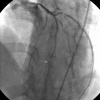

ECG is still the first diagnostic tool for coronary artery disease. It is possible to predict the localisation of affected vessel(s) through ST and T changes on ECG. Sometimes, reciprocal changes may be the only marker of acute myocardial ischaemia, as single T-wave inversion in lead aVL may represent a coronary artery lesion in the left anterior descending (LAD). A 49-year-old woman presented to the emergency department, with left-sided chest pain. Her initial ECG showed no ischaemic changes. On the third hour ECG there was T-wave inversion in leads aVL and V2, and troponin turned positive. Coronary angiography showed 90% mid-LAD occlusion. The importance of this case is that patients with ischaemic chest pain should be followed with serial ECG. Also, emergency physicians should be alert to identify new changes on ECG, as isolated T-wave inversion in lead aVL can be the only finding to take the patient into the catheterisation laboratory.